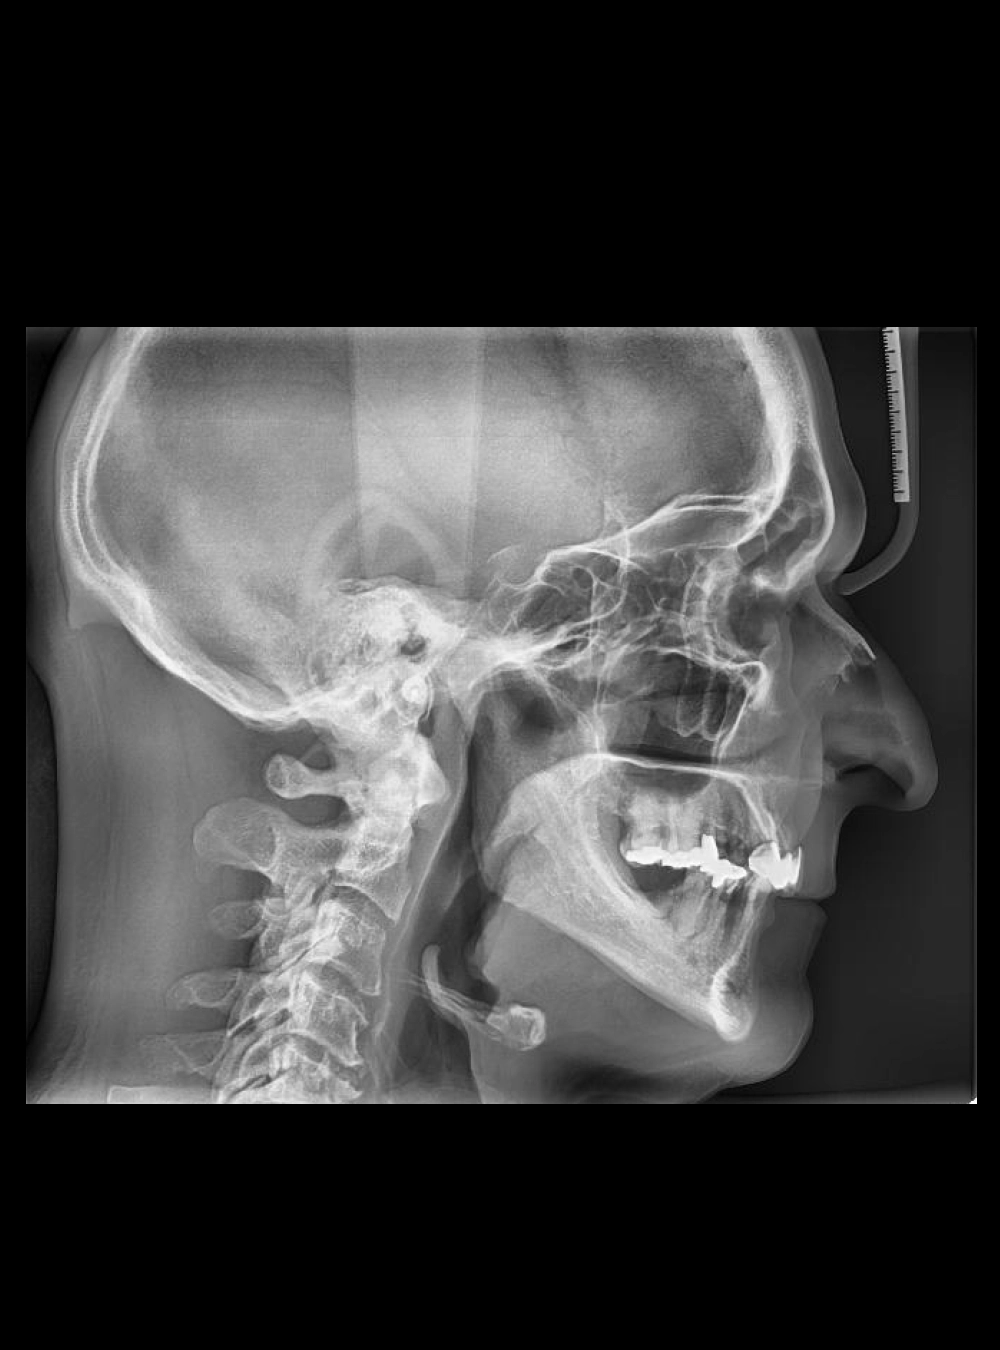

Lateral de Cráneo

• Lateral de Cráneo